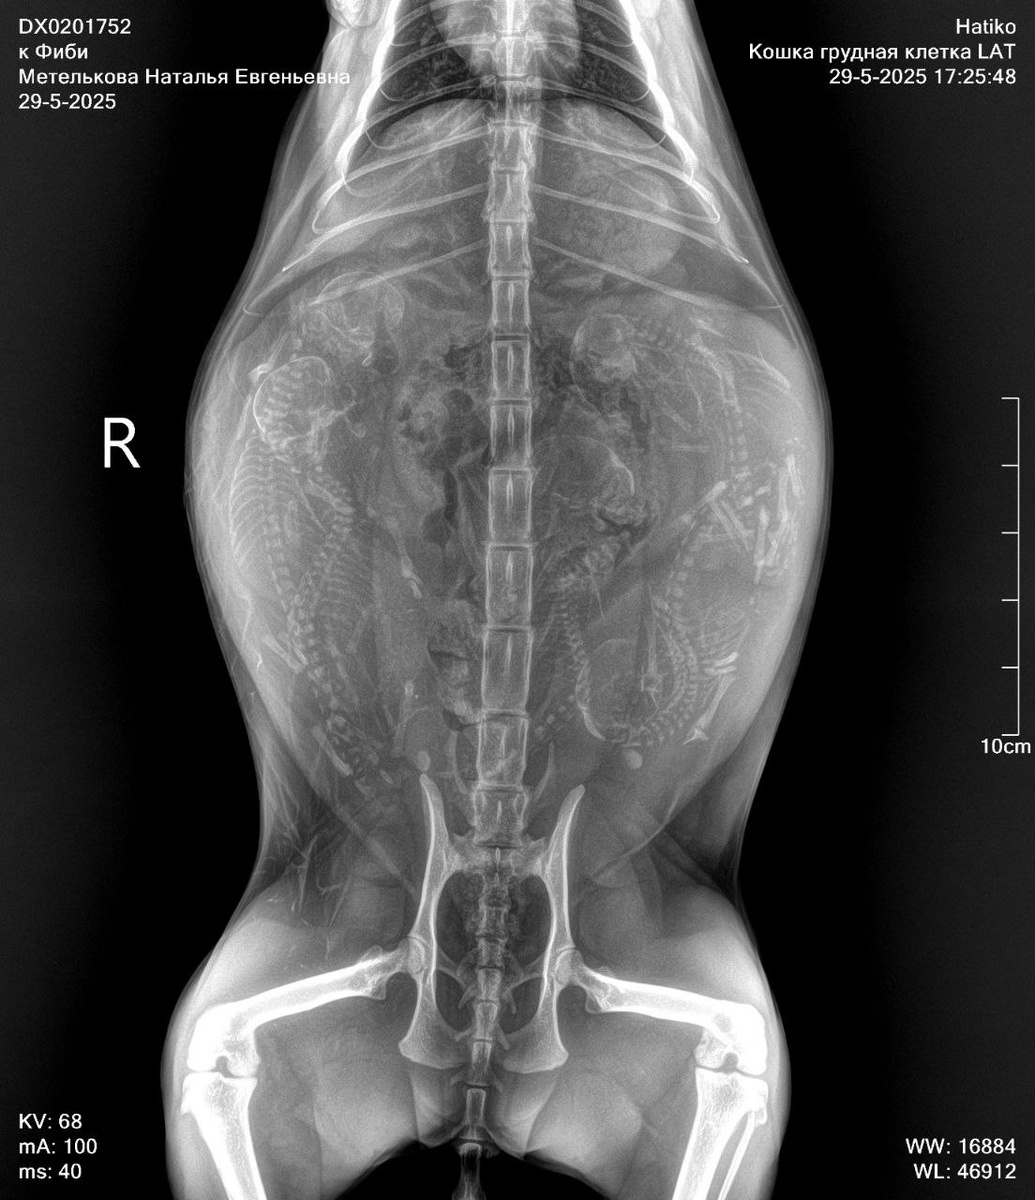

Всем доброго дня и хорошего настроения! Фиби ездила вчера в клинику Хатико к нашей несравненной Буссе. Мы делали контрольное УЗИ и рентген аж в двух проекциях. Приблизительная дата родов у нашей девочки 6 июня получилась. Кунгурова (лучший репродуктолог, которая живёт и принимает в другом городе) сказала, что 3-4. Но котятки уже крупные и в маме буквально безастановочно пляшут, обе ничего не гарантируют. Никаких паталогий нет, развитие плодов отличное. Все в норме, а это самое главное для нас! Также, как известно, узи, даже рентген не дает гарантии - что количество котят укажут точное. Есть только один точный способ узнать сколько котят в матери - кесарево и руки хирурга. Я хотела бы запустить опрос - как вы считаете, сколько котят у Фиби в животике. Прикрепляю рентген в двух проекциях. Давайте вместе попробуем угадать :) Ответ будет точным! Но после родов 😂

Я хотела бы запустить опрос - как вы считаете, сколько котят у Фиби в животике. Прикрепляю рентген в двух проекциях.